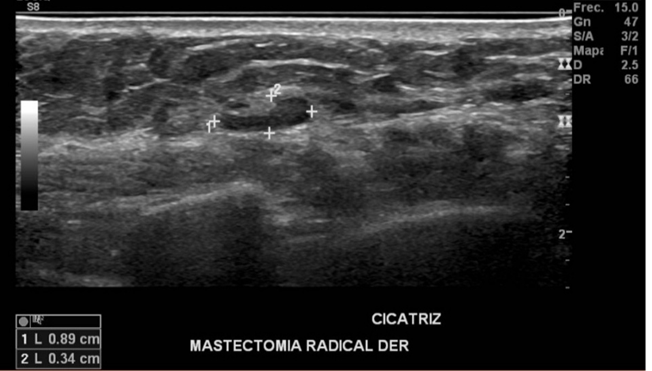

Se evalúa en forma dirigida sitio de mastectomía derecha, observándose presencia de linfonodo de tamaño y morfología normal en región de cicatriz.

Probable linfonodo en región de cicatriz de mastectomía derecha.